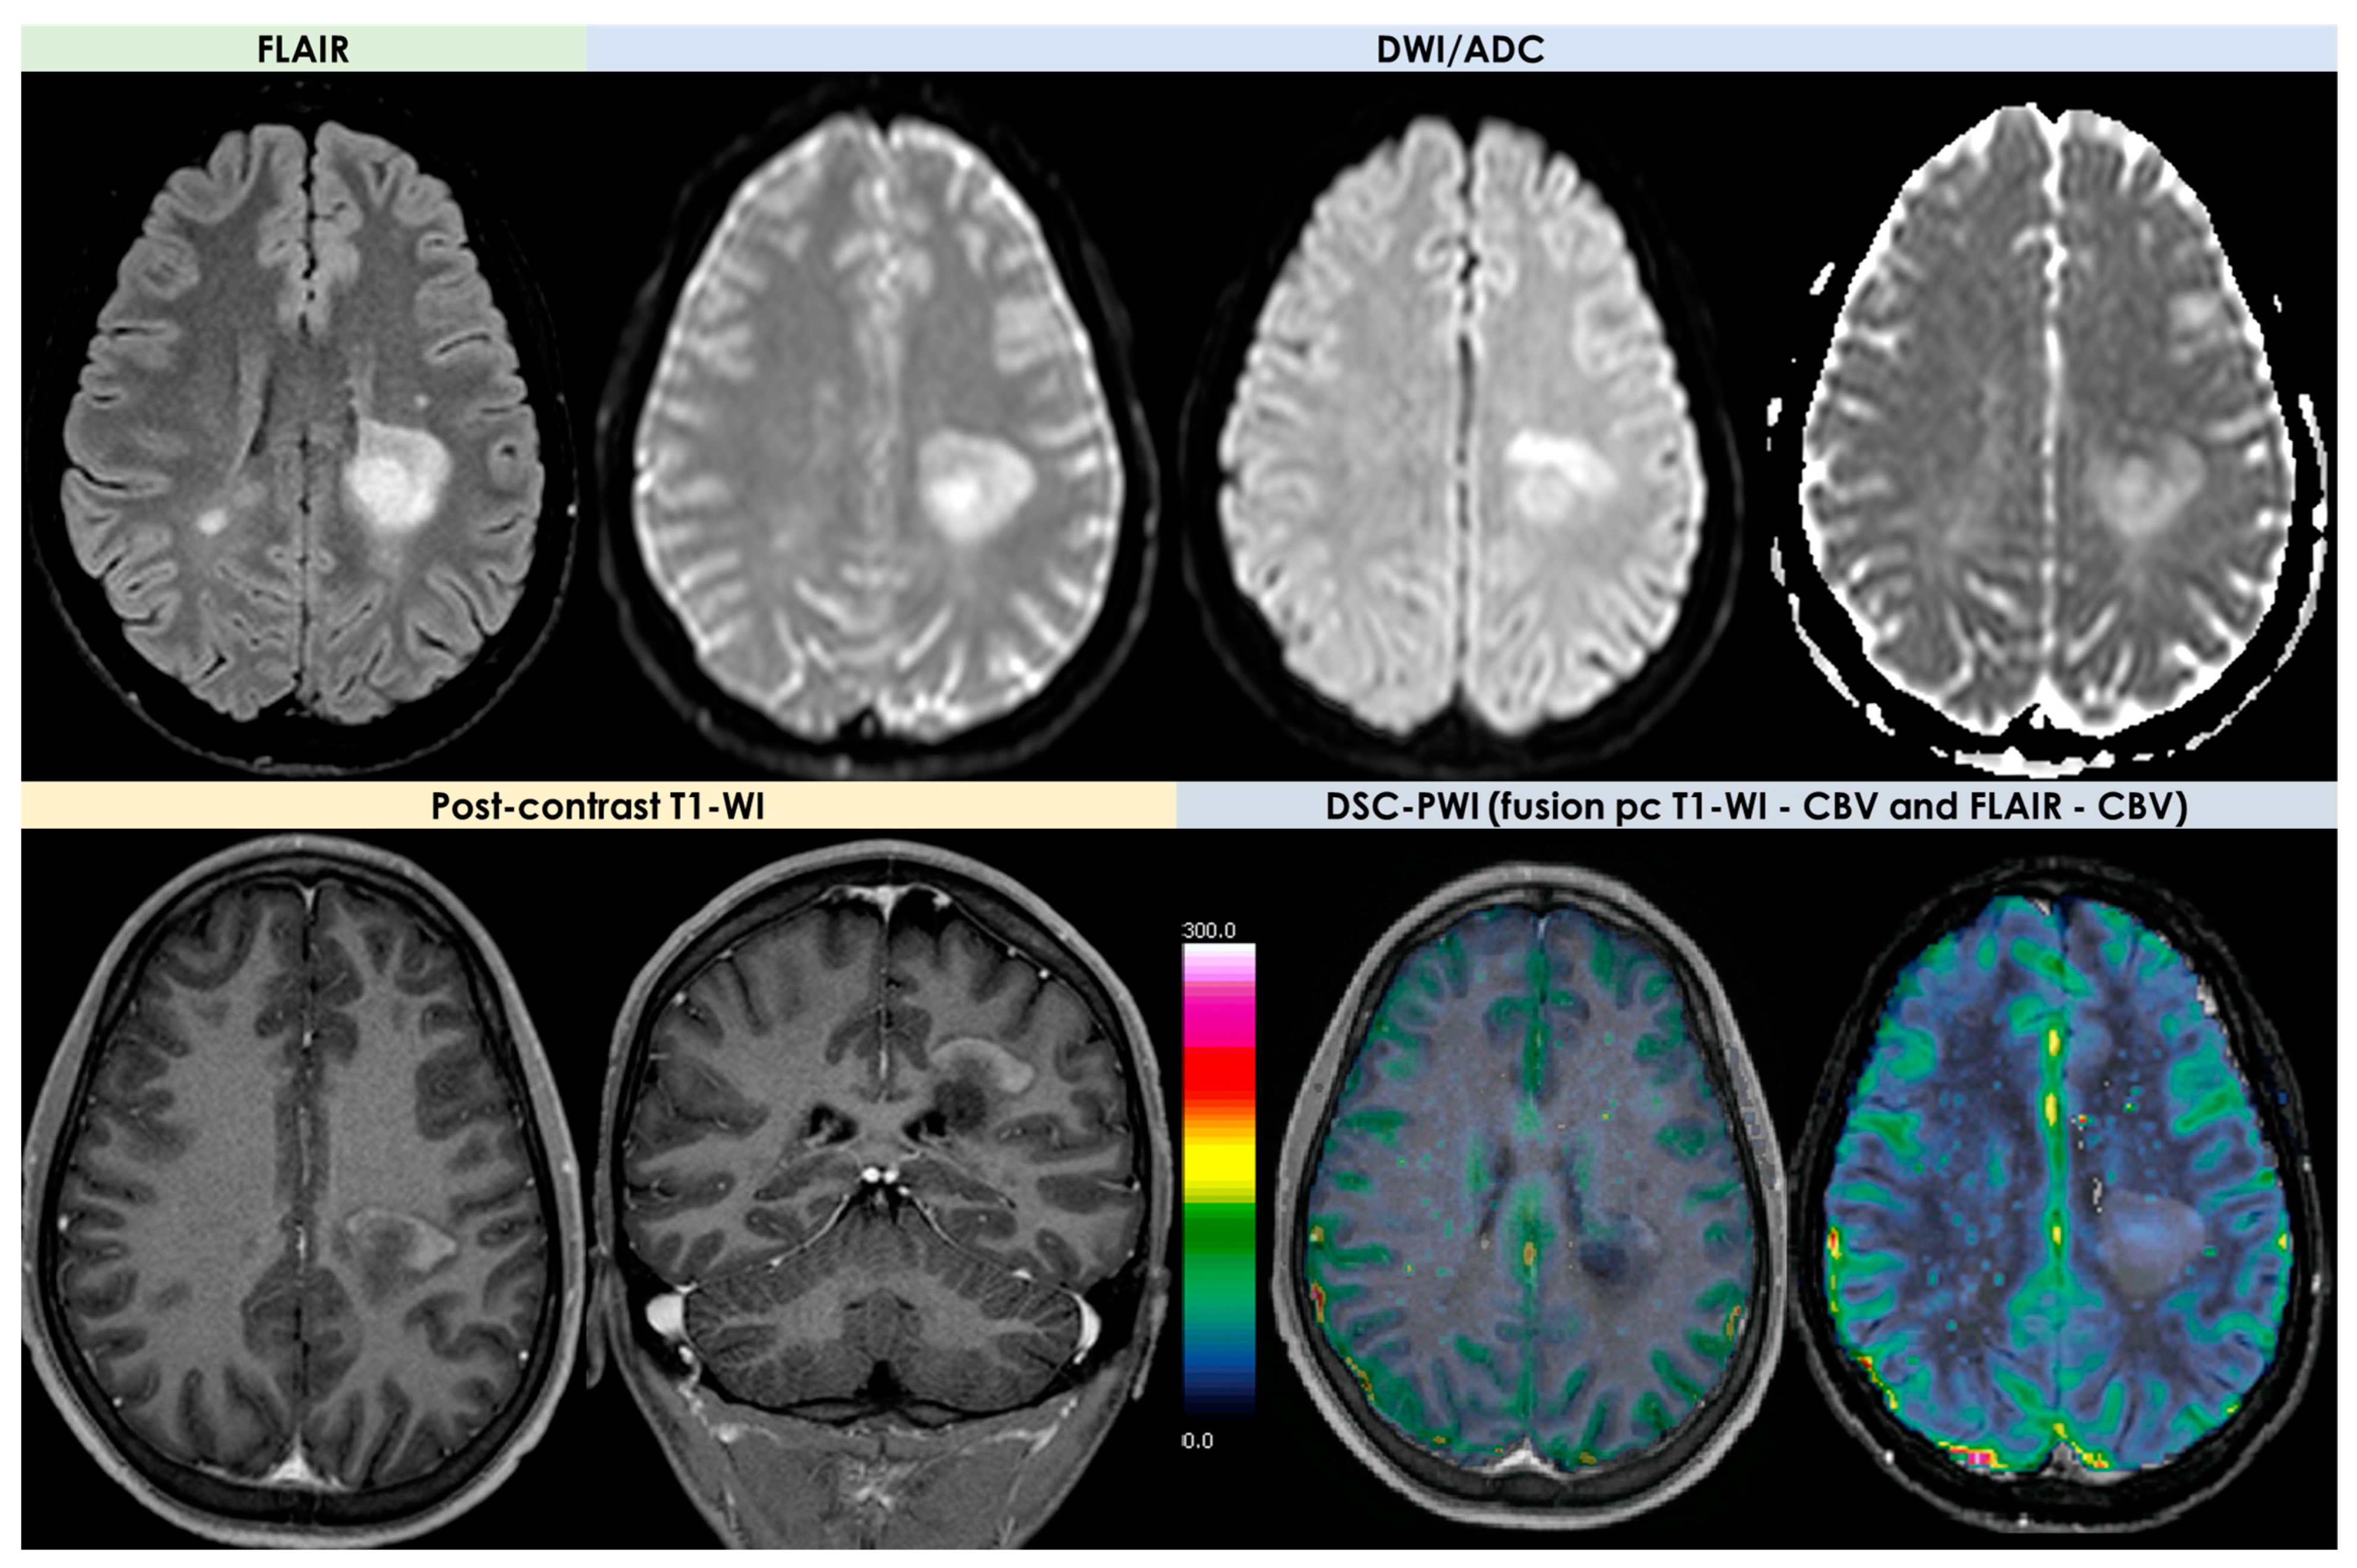

- -

- An open-ring or incomplete-rim enhancement;

- A closed ring or complete rim enhancement;

- A T2 hypointense rim;

- An absent or mild mass effect;

- Absent or mild perilesional edema.

| Open-ring or incomplete-rim enhancement | 35% (24–47%) |

| Closed-ring or complete-rim enhancement | 18% (11–29%) |

| T2 hypointense rim | 48% (36–60%) |

| Absent or mild mass effect | 67% (48–83%) |

| Absent or mild perilesional edema | 57% (36–76%) |

| DWI/ADC | Hyperintense on DWI/hypointense on ADC maps Decreased FA values in lesions | High ADC values in center of lesion and relatively low ADC values in periphery of lesion Threshold for the minimum ADC value for distinguishing TDLs from PCNSL is 0.556 × 10−3 mm2/s | Hypointense in DWI and ADC | Hypointense on DWI and ADC | “Eccentric target sign” consisting of an eccentric nodule along the rim of an enhancing lesion on T1-WI ADC > 1.6 × 10−3 mm2/s suggestive of toxoplasmosis |

| DSC-MRI | rCBV lower than HGG Characteristic TIC | Few data with variable findings | rCBV usually higher than PCNSL, but variable findings | No data | rCBV lower than that in necrotic glioblastomas and metastases |